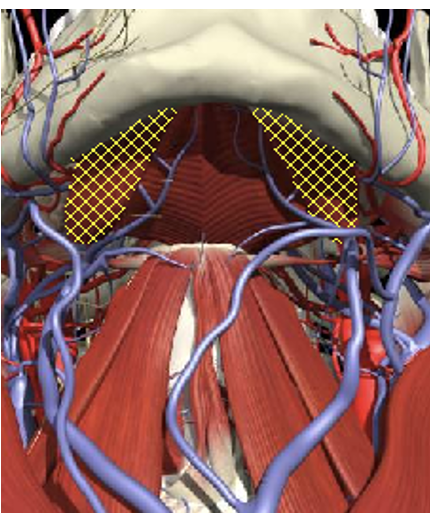

Scalenes

Submentals

Sub-Occipital

Obliquus Capitis Inferior

-

The C2 vertebral level is identified as a plane 2.5 cm below the mastoid process (3.0 cm below the occipital bone).

Midway between the posterior border of the sternomastoid and the dorsal midline. Depth of 3.0-3.5 cm.